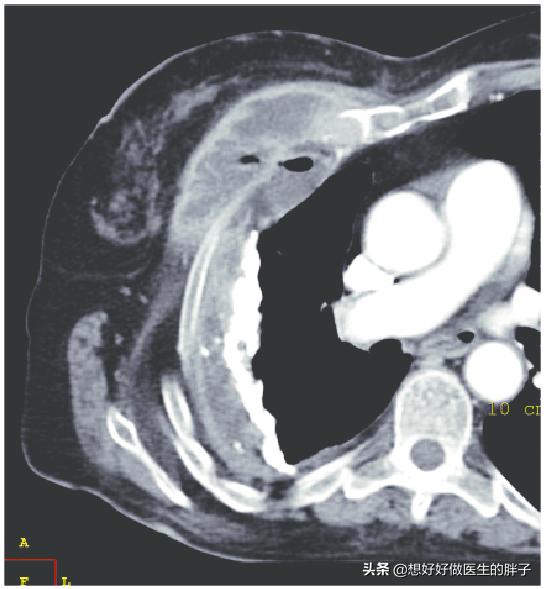

CTスキャンは、小さな腫瘍や結核マイコプラズマ肺炎などを発見することができる。

9ミリのin situ腺がんは、自覚症状もなく、身体機能もすべて正常だが、CTでしか早期発見できず、手術で切除した。

このような器具を使わず、聴診器だけでは、3~5年後に進行した段階で発見されるのが怖い。

こうした先進的な装置により、肺がんの5年生存率は過去20年間で8%から20%近くまで上昇した。今後数年間で、より多くの人々が早期がん検診に注意を払えば、この数字は劇的に上昇することは間違いない!かつての胃がんの予防と制御のように。